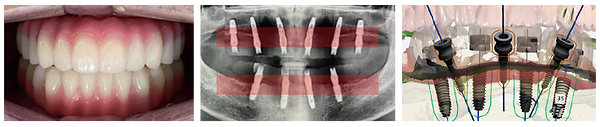

전체 임플란트는 심한 치주질환이나 외상, 충치 등의 다양한 이유로 모든 치아가 상실된 경우 14 개 정도의 임플란트를

식립하여 상실된 치아 기능을 회복시키는 시술입니다.

전체 치아를 임플란트로 식립하는 만큼 난이도가 아주 높은

시술이며 경험이 많은 전문의의 수준 높은 임상경험과

기술력이 필요합니다.

전체 임플란트는 심한 치주질환이나 외상, 충치 등의 다양한 이유로 모든 치아가 상실된

경우 14 개 정도의 임플란트를 식립하여 상실된 치아 기능을 회복시키는 시술입니다.

전체 치아를 임플란트로 식립하는 만큼 난이도가 아주 높은 시술이며 경험이 많은

전문의의 수준 높은 임상경험과 기술력이 필요합니다.